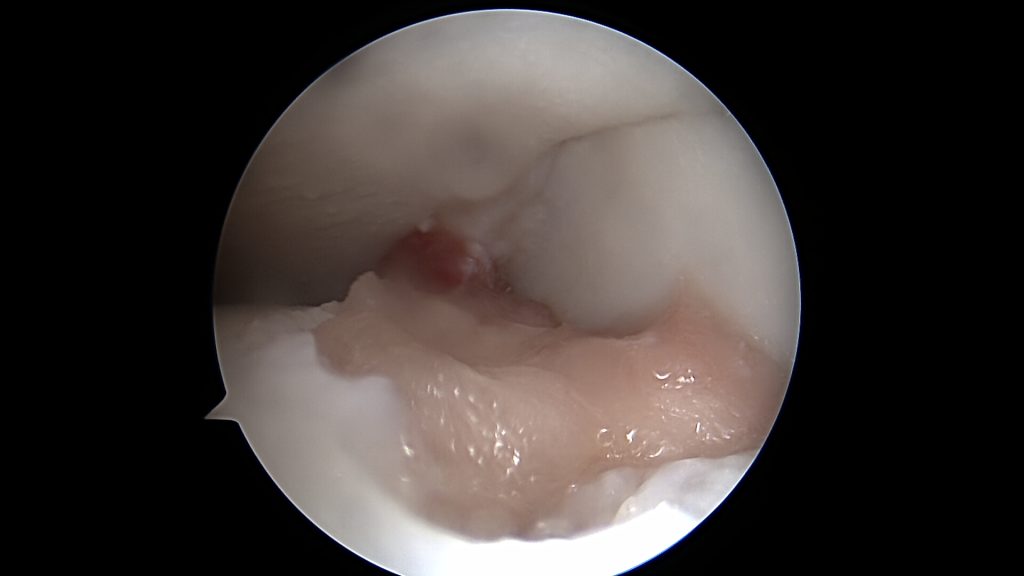

Leczenie operacyjne polega na oczyszczeniu oraz odświeżeniu dna ubytku oraz wypełnieniu go materiałem Hyalofast, dedykowanym do uszkodzeń chrzęstno-kostnych. W niektórych przypadkach (młody wiek oraz duża wielkość fragmentu) możliwe jest ponowne przytwierdzenie wydzielonego fragmentu chrzęstno-kostnego OCD, jeśli nie uległ on wcześniej zniszczeniu.

Po wypełnieniu miejsca ubytku implantuje się komórki macierzyste, które na bazie usieciowanego kwasu hyaluronowego wytwarzają regenerat chrzęstny.